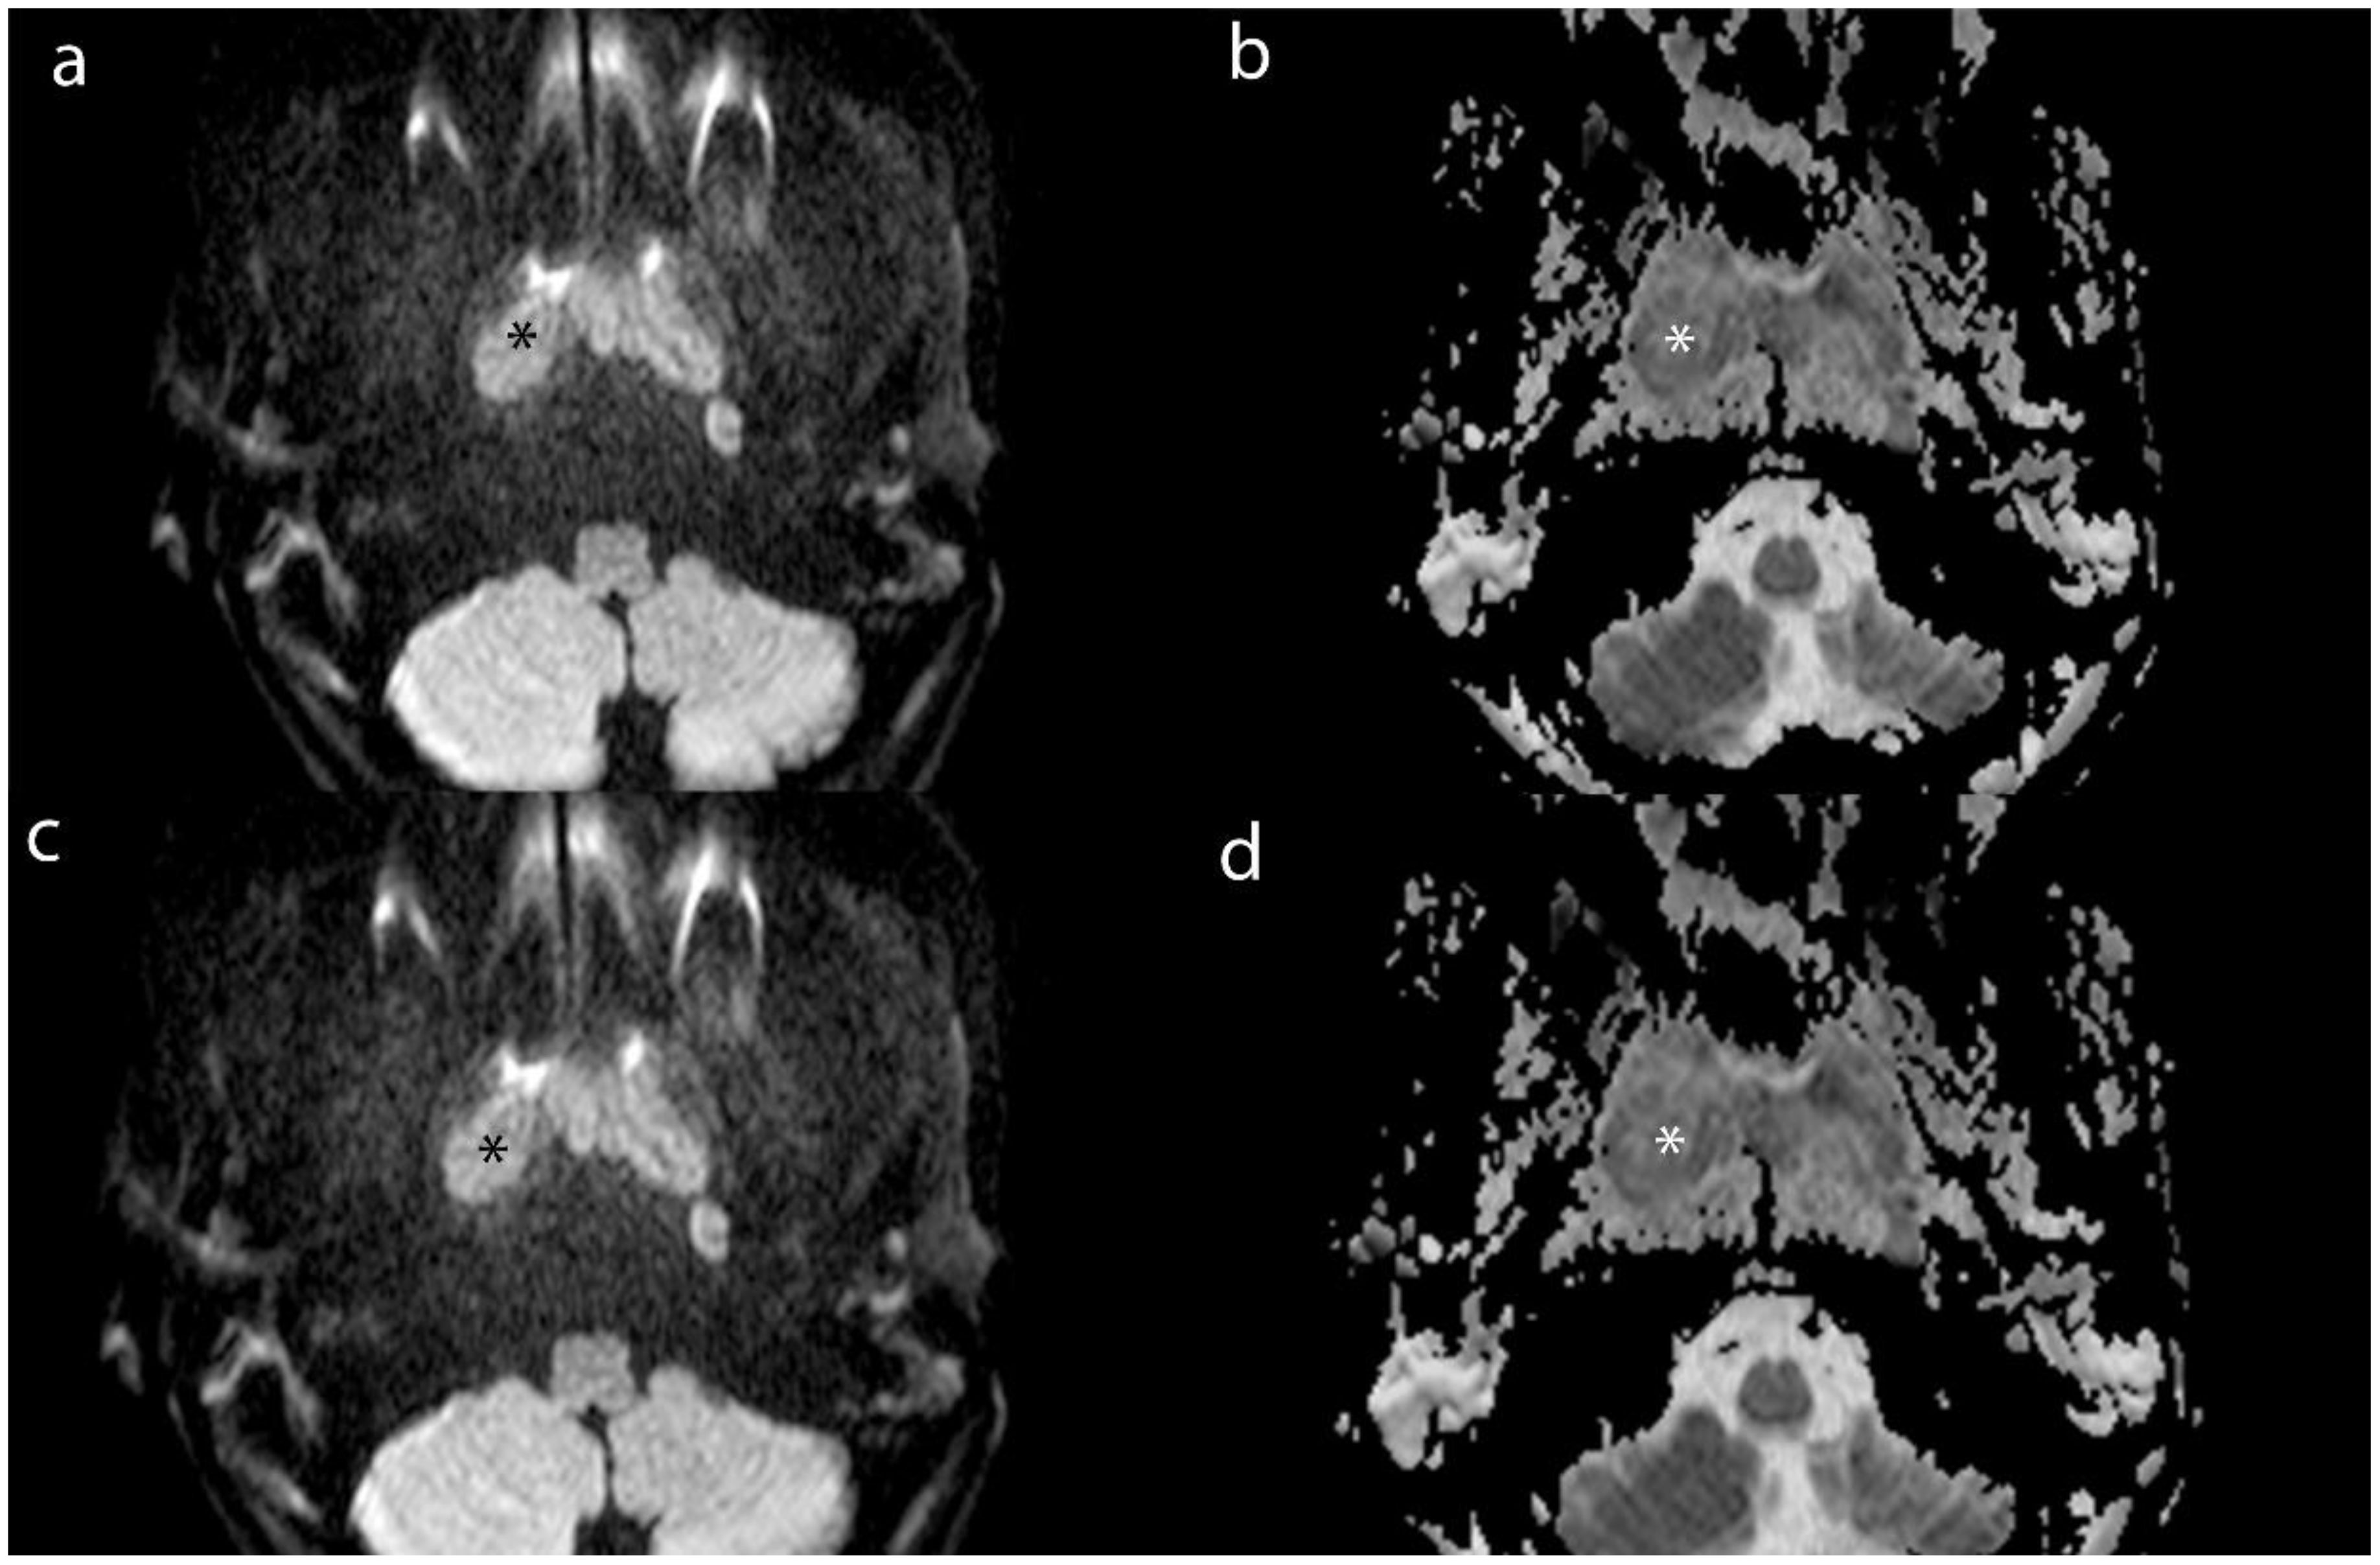

Purpose: To explore the value of dual-energy CT (DECT) in evaluating the efficacy of nasopharyngeal carcinoma (NPC) and in the detection of metastatic lymph nodes (MLNs). Materials and Methods: For this retrospective study, we collected and analyzed clinical and imaging data from 83 patients diagnosed with NPC via histopathology, who were admitted to the Radiotherapy Department from August 2022 to July 2024. The cohort consisted of 64 males and 19 females, with an average age of 50.86±13.45 (years). All patients underwent DECT enhancement and MRI scanning before and after the first treatment course to assess the extent of lesions and lymph nodes (LNs). A total of 423 LN imaging datasets were analyzed. We measured iodine concentration (IC), effective atomic number (Zeff), electron density (ED), and normalized iodine concentration (NIC). Additionally, we recorded the magnetic resonance ADC values of the LNs. Results: Statistical analysis of Zeff, ED, and NIC values of lesion and LNs revealed no significant differences between groups (p > 0.05). The Zeff, ED, and NIC values for lesions and LNs were significantly lower after treatment than before (p < 0.05). Receiver operating characteristic (ROC) analysis for MLNs indicated that the area under the ROC curve (AUC) for NIC indicated high accuracy. Conclusion: DECT provides valuable functional parameters for assessing the efficacy of NPC and demonstrates significant clinical application value. Notably, the NIC parameter shows high diagnostic efficacy for MLNs, comparable to the ADC value obtained from MRI.